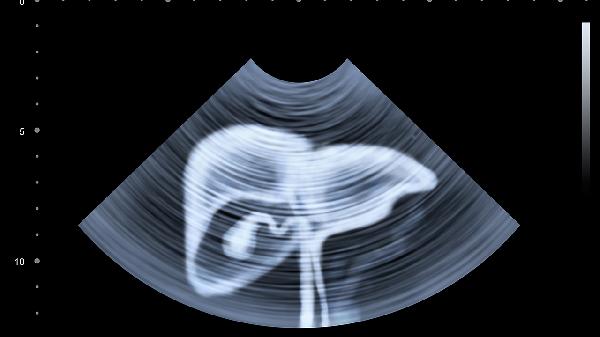

五個癥狀表明肝臟可能有問題

肝臟問題可能表現(xiàn)為皮膚黃染、食欲減退、乏力、腹脹、尿液顏色加深等癥狀。肝臟是人體重要的代謝器官,當肝臟功能受損時,可能出現(xiàn)上述癥狀,建議及時就醫(yī)檢查。